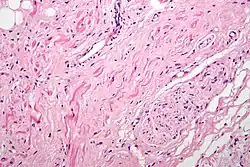

H&E stained fibers of the vagus nerve (bottom right) innervate the sinoatrial node tissue (middle left)

Parasympathetic innervation of the heart is partially controlled by the vagus nerve and is shared by the thoracic ganglia. Vagal and spinal ganglionic nerves mediate the lowering of the heart rate. The right vagus branch innervates the sinoatrial node. In healthy people, parasympathetic tone from these sources is well-matched to sympathetic tone. Hyperstimulation of parasympathetic influence promotes bradyarrhythmias. When hyperstimulated, the left vagal branch predisposes the heart to conduction block at the atrioventricular node.